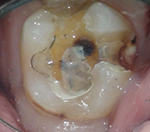

上のような小さな歯が、マイクロスコープではこのように見えています。

むし歯の治療(カリエス処置)

指の先ほどの歯の中の、むし歯の部分だけを除去しなければなりません。

むし歯の部分を取り損ねたら再発し、削り過ぎると歯を弱くしてしまうので、注意力と集中力が必要です。

マイクロスコープを用いれば視野を拡大して見られるため、健康な歯を痛めずむし歯の部分だけを除去できます。